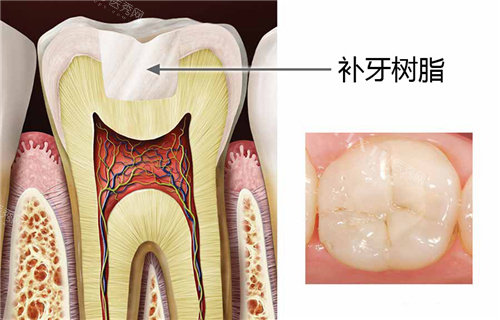

普通树脂补牙是台州多数口腔机构的基础项目,适合牙齿浅龋、小面积缺损的修复。其价格主要受材料品牌和机构定位影响,具体参考如下:

二、台州进口树脂补牙价格表:材料升级,美观与耐用双提升

进口树脂因材料稳定性高、色泽自然,更受对美观和长期使用有要求的患者青睐。台州市场主流进口树脂品牌及价格如下: